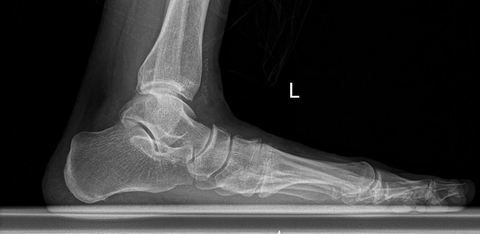

Arkadaşlar merhaba, haziran sonuna doğru tecilim bitiyor. Yoklama işlemlerini halledip sağlık kontrolüne girip muafiyet almak istiyorum. Başlıktan anlaşılacağı üzere düz tabanım ve bundan dolayı bacaklarımda, belimde, aşil tendonumda, ayak kemerimde, tarsal kemiklerde ağrılarım olmakta(kuboid sendromum var). Maalesef 5 dk bile yürümeye kalksam veya bir süre ayakta sabit dursam ayağımın ortası ağrımaya başlıyor. Ayağımın röntgenini henüz çektiremedim ancak dışarıdan çekilmiş fotoğraflarını yükledim. Daha önce bu hususta muafiyet almış veya bilgisi olan arkadaşlar beni bu hususta aydınlatabilirse çok sevinirim. Sağlıklı günler dilerim. ![]() ![]() < Bu mesaj bu kişi tarafından değiştirildi sosyaliçici -- 3 Haziran 2024; 16:23:34 > |